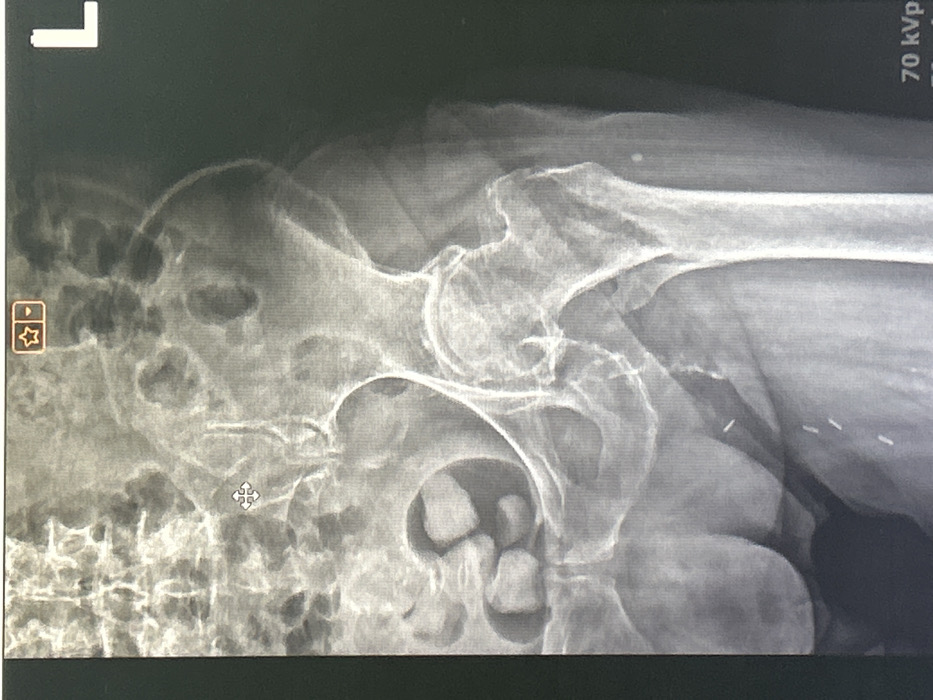

This image is a photograph of a digital anteroposterior radiograph displaying a human pelvis and proximal left femur, originating from the city of Ruse, Bulgaria. The "L" marker in the upper right corner confirms the left anatomical side. The radiograph clearly visualizes the left ilium, ischium, pubis, sacrum, femoral head, neck, and proximal femoral shaft. The left hip joint space appears narrowed with evidence of osteophyte formation, indicative of degenerative changes. Multiple ovoid, radiopaque densities are present in the right lower quadrant of the pelvic cavity, consistent with calcified structures. Additionally, at least three small, linear, radiopaque metallic objects are observed within the soft tissues of the left superior thigh/groin region. Technical exposure parameters, "70 kVp" and "mA," are visible in the bottom right corner. Interface elements such as a crosshair cursor and bookmark icons are present at the top, indicating the image is captured from a digital medical imaging workstation screen. No individuals or direct actions are depicted beyond the displayed medical scan.